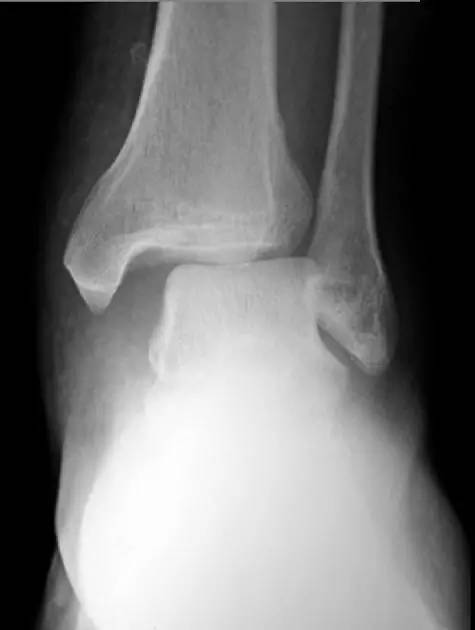

6. Pilon 骨折

涉及负重关节面(胫距关节面)与胫骨远侧干骺端的骨折。其典型特征是干骺端存在不同程度的压缩、干骺端的压缩粉碎性骨折不稳定、原发性关节软骨损伤以及永久性关节面不平整导致预后不良。

pilon 骨折正位片

pilon 骨折侧位片

pilon 骨折三维 CT 表现